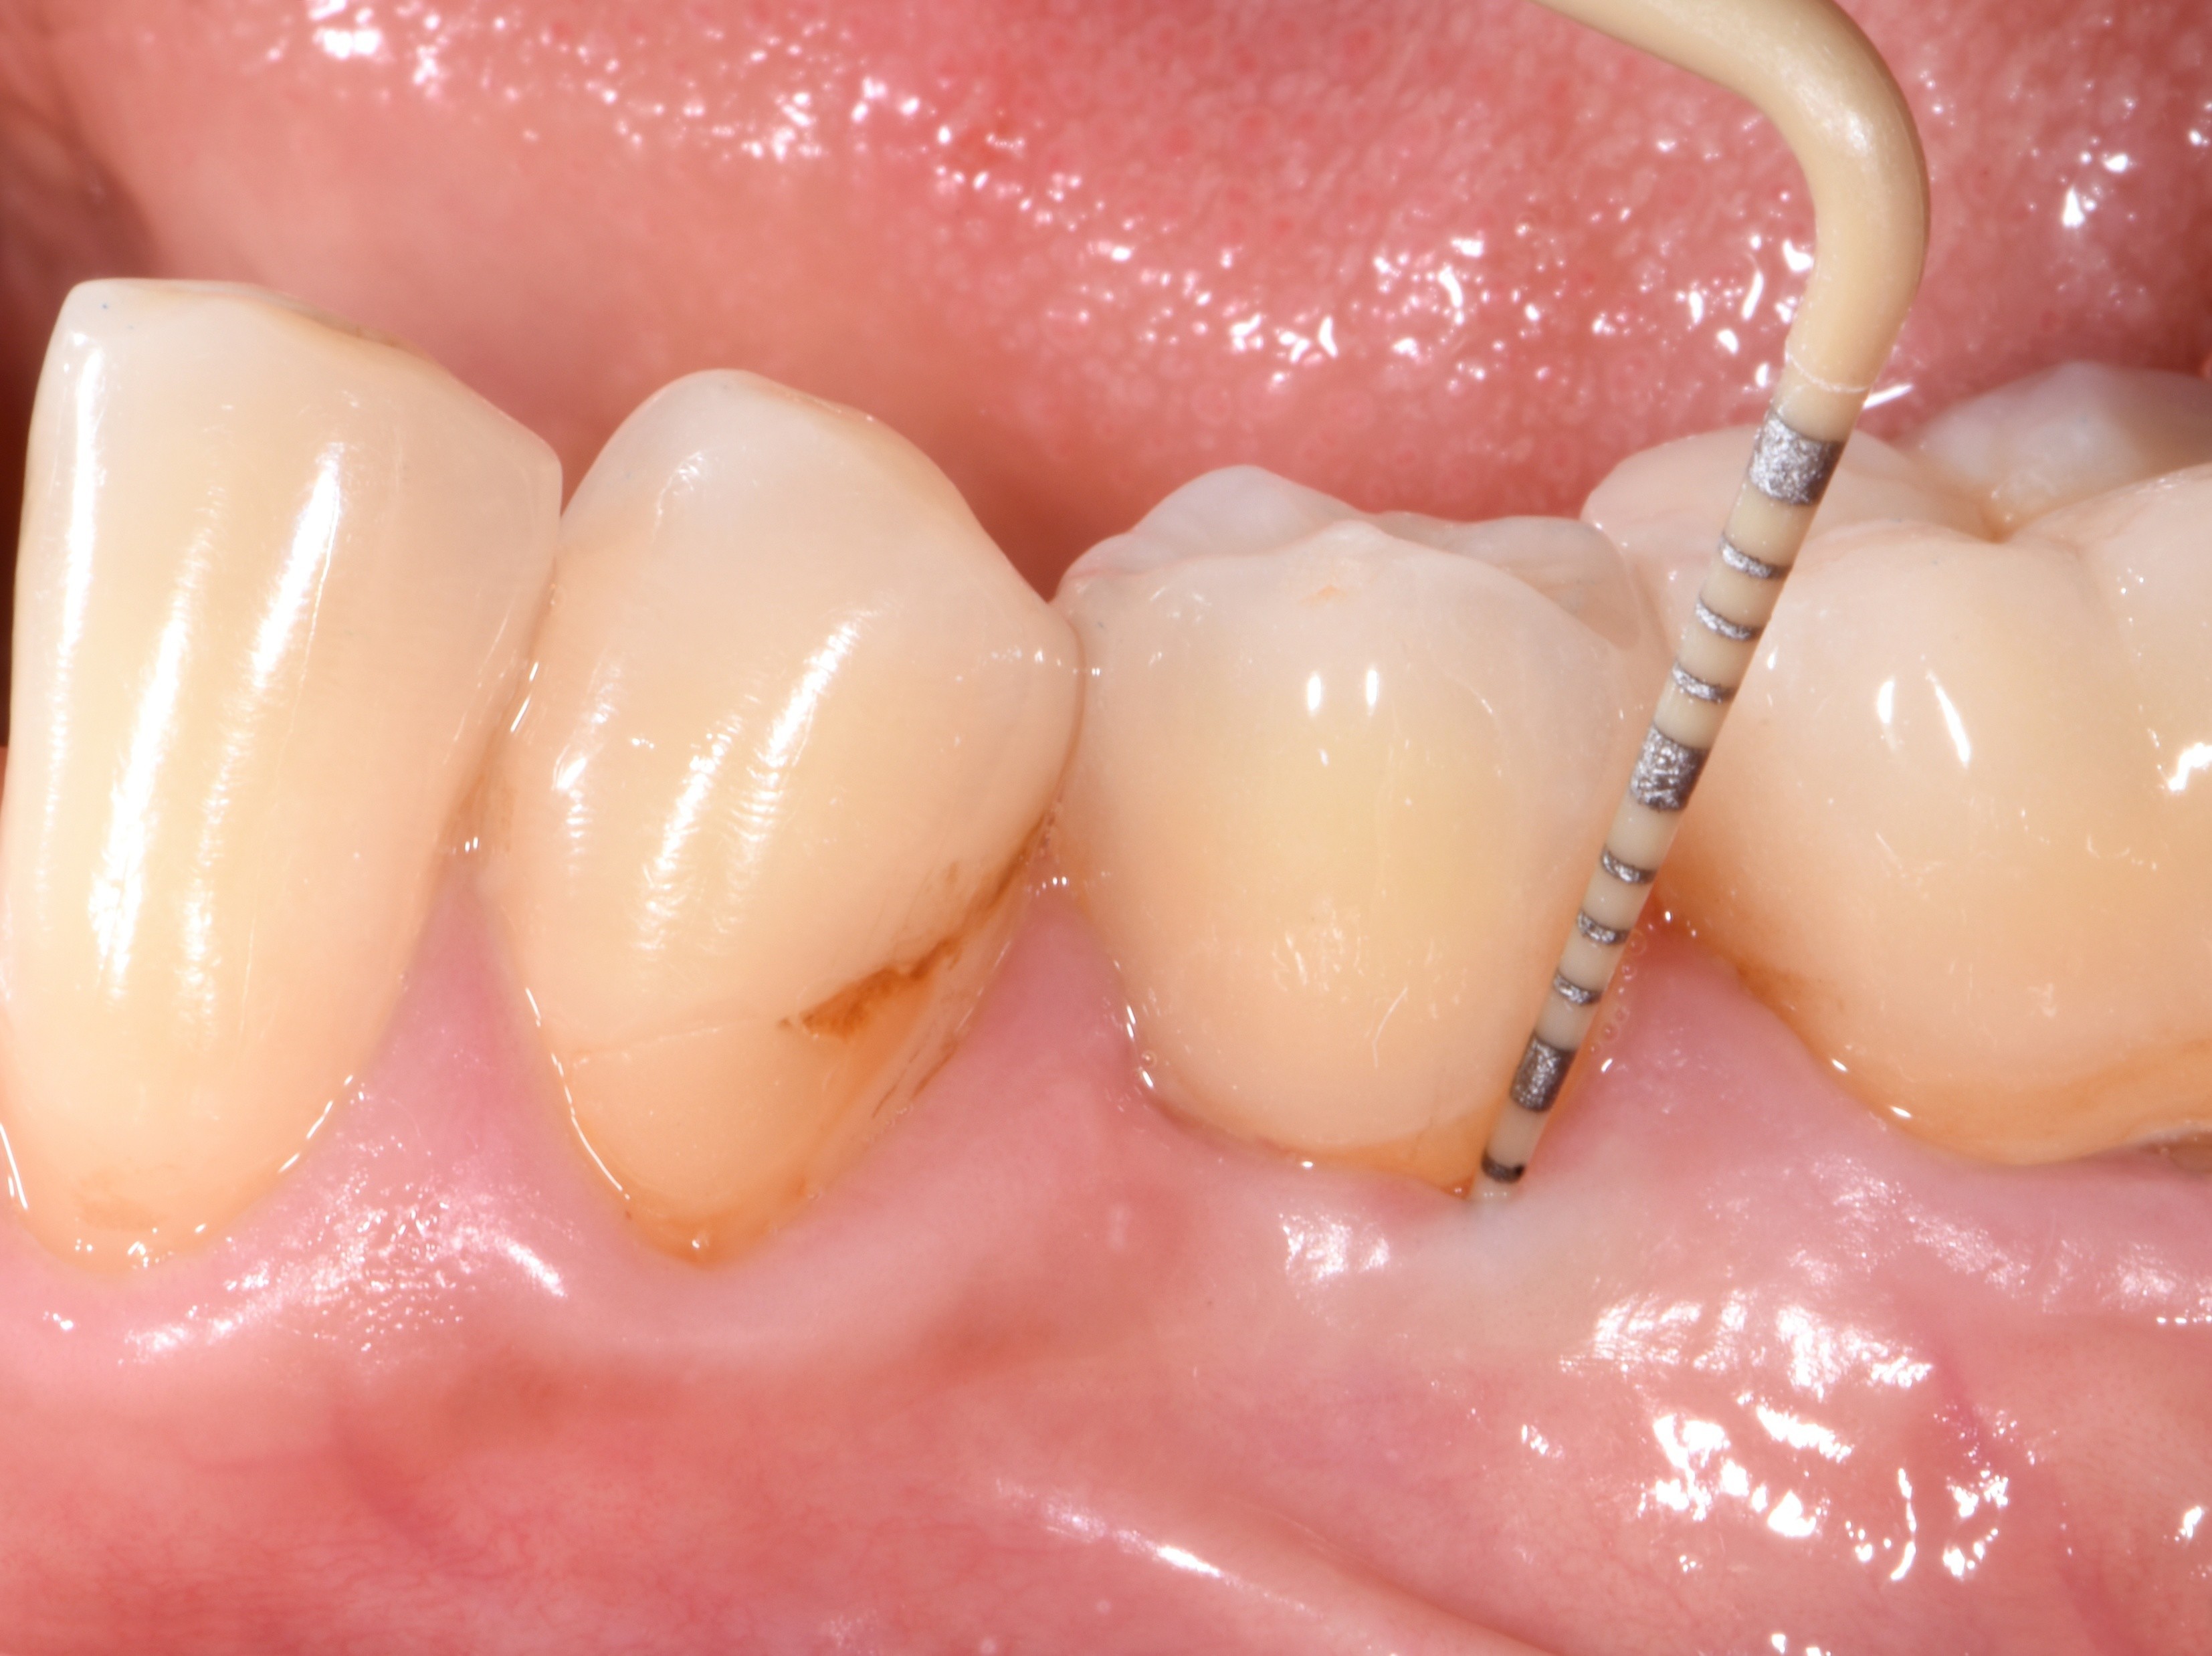

Ein kronenversorgter Patent™ Symbionic Tooth bei einem Patient mit Risikofaktoren (Rauchen, Diabetes Typ II, schlechte Mundhygiene und Polymedikation) nach 4.5 Jahren:

Die flache Sondierungstiefe von 3 mm entspricht der Definition eines gesunden natürlichen Zahns (© Dr. Roland Glauser).